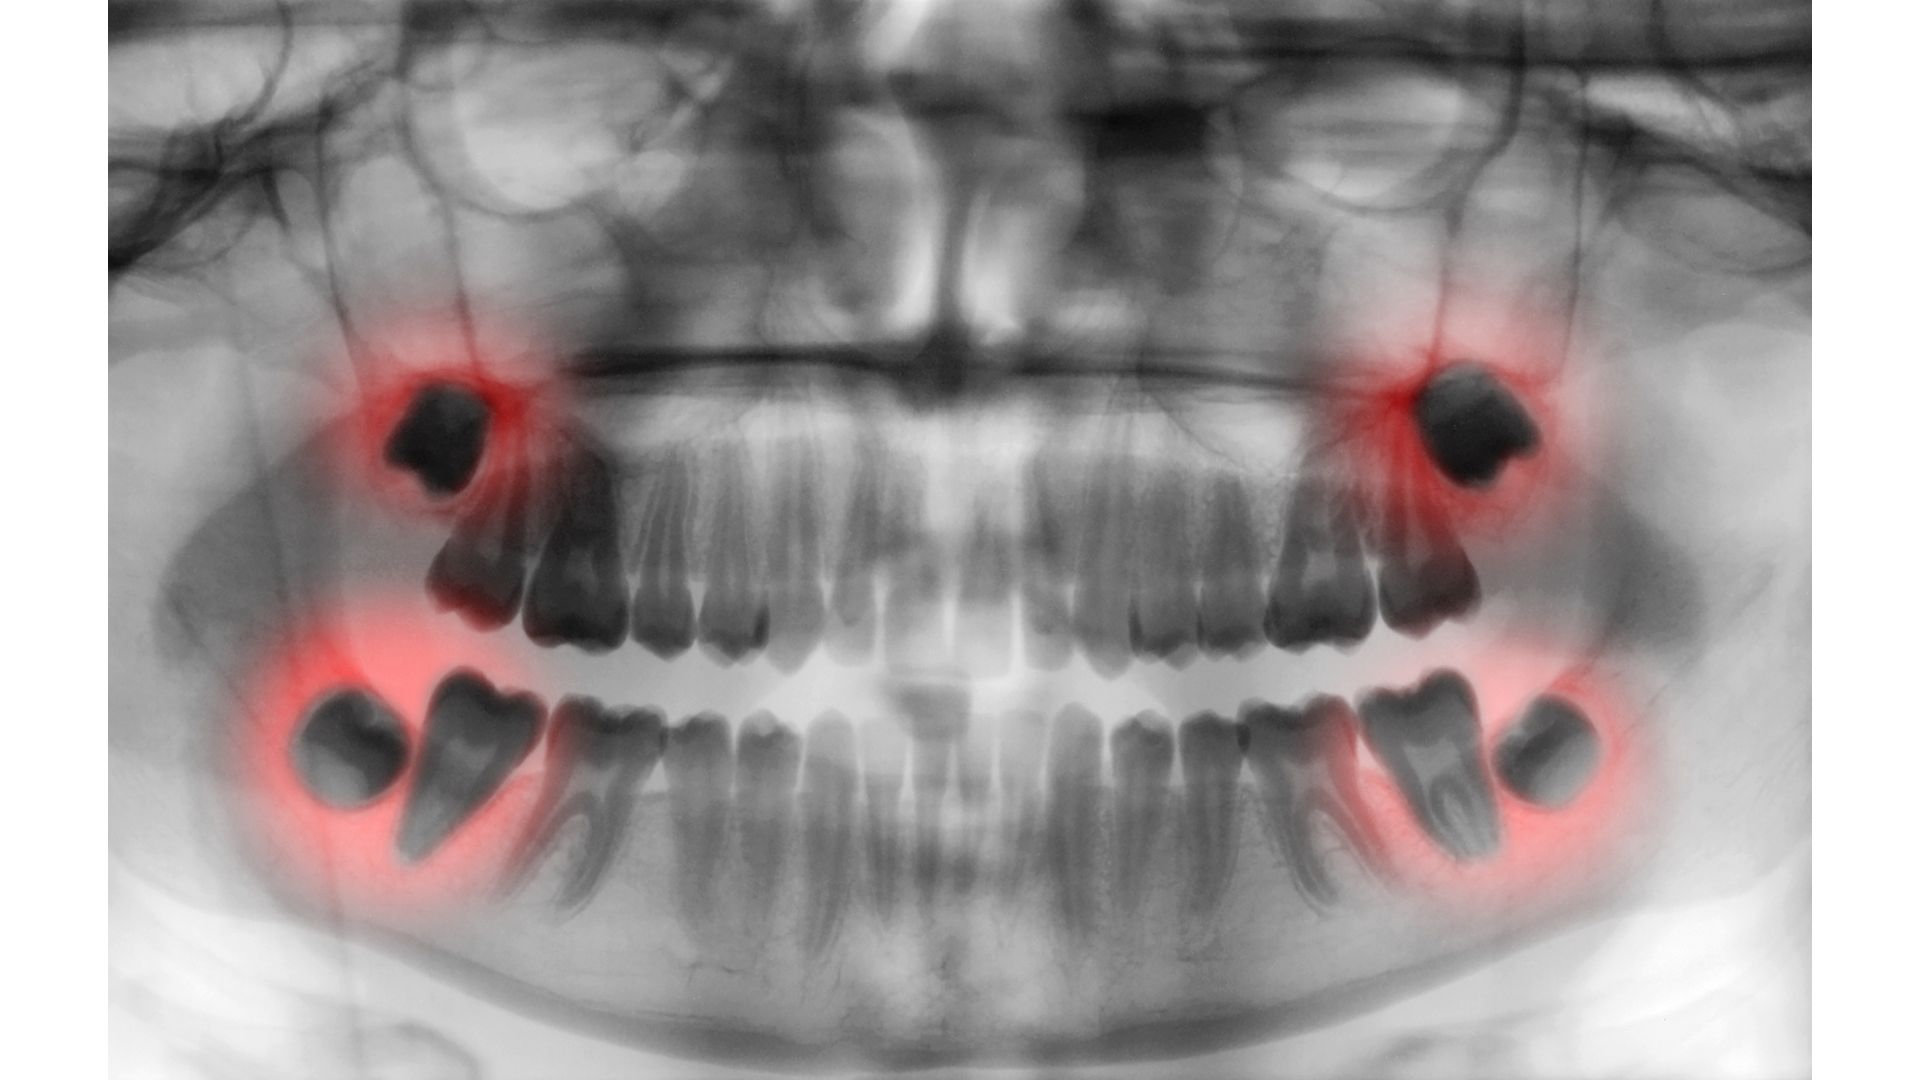

親知らず